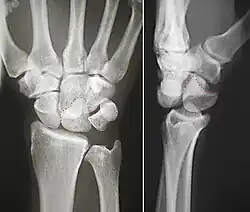

![]() Left hand anterior view (palmar view). Lunate bone shown in red. | |

The lunate bone (semilunar bone) is a carpal bone in the human hand. It is distinguished by its deep concavity and crescentic outline. It is situated in the center of the proximal row carpal bones, which lie between the ulna and radius and the hand. The lunate carpal bone is situated between the lateral scaphoid bone and medial triquetral bone.

The lunate is a crescent-shaped carpal bone found within the hand. The lunate is found within the proximal row of carpal bones. Proximally, it abuts the radius. Laterally, it articulates with the scaphoid bone, medially with the triquetral bone, and distally with the capitate bone. The lunate also articulates on its distal and medial surface with the hamate bone.[2]: 708 [3]

The proximal surface of the lunate bone is smooth and convex, articulating with the radius. The lateral surface is flat and narrow, with a crescentic facet for articulation with the scaphoid bone. The medial surface possesses a smooth and quadrilateral facet for articulation with the triquetral bone. The palmar surface is rough, as is the dorsal surface. The dorsal surface is broad and rounded. The distal surface of the bone is deep and concave.[4]